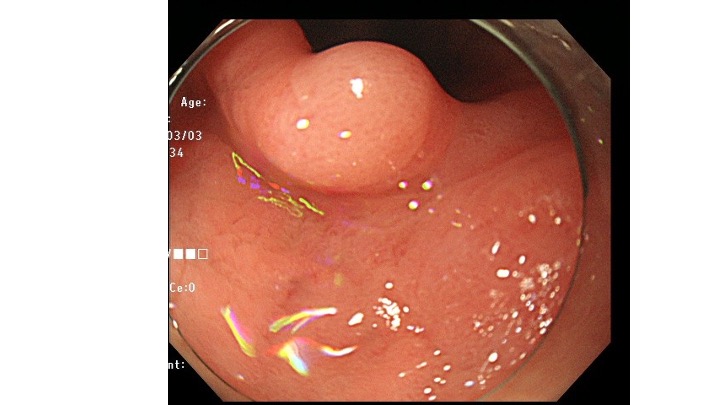

今回提示する症例(ピロリ除菌後)は、隆起型の早期胃癌で、表層に癌の露出を認めない早期胃癌です。

胃内には複数の胃底腺ポリープが散見されます。良性で取る必要のないポリープです。

前庭部の隆起は、良性ポリープではなく、癌疑いで生検しましたが、結果は Group1の結果でした。